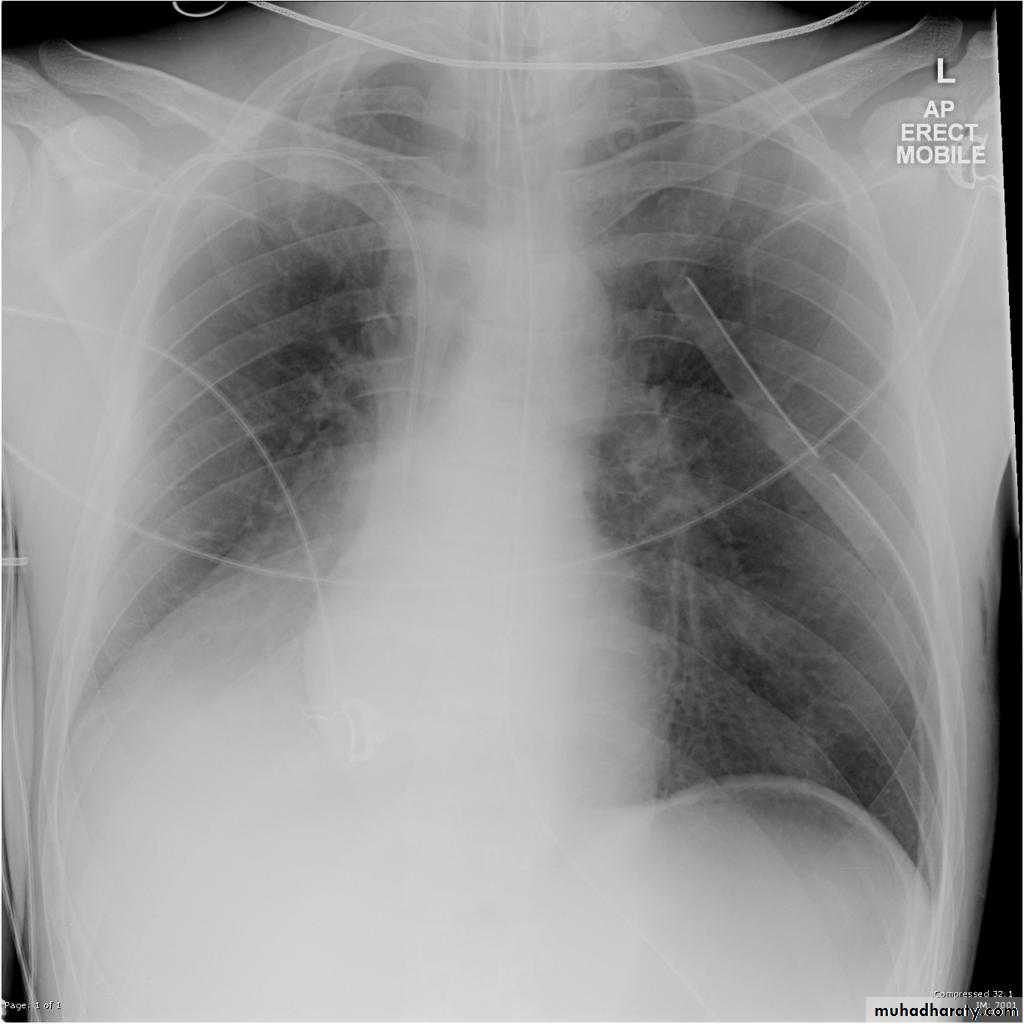

Left lower lobe collapse has distinctive features, and can be readily identified on frontal chest radiographs, provided attention is paid to the normal cardiomediastinal contours. The shadow cast by the heart does however make it harder to see than the right lower lobe collapse

Radiographic features

Left lower lobe collapseis readily identified in a well penetrated film of a patient with normal sized heart, but can be challenging in the typical patient with collapse, namely unwell patients, with portable (AP) often under-penetrated films, often with concomitant cardiomegaly. Features to be observed include :

triangular opacity in the posteromedial aspect of the left lung

edge of collapsed lung may create a 'double cardiac contour'

left hilum will be depressed

loss of the normal left hemidaphgragmatic outline

loss of the outline of the descending aorta

Non-specific signs indicating left sided atelectasis are usually also be present including:

elevation of the hemidiaphragm

crowding of the left sided ribs

shift of the mediastinum to the left

On lateral projection the left hemidiaphragmatic outline is lost posteriorly and the lower thoracic vertebrae appear denser than normal (they are usually more radiolucent than the upper vertebrae) .